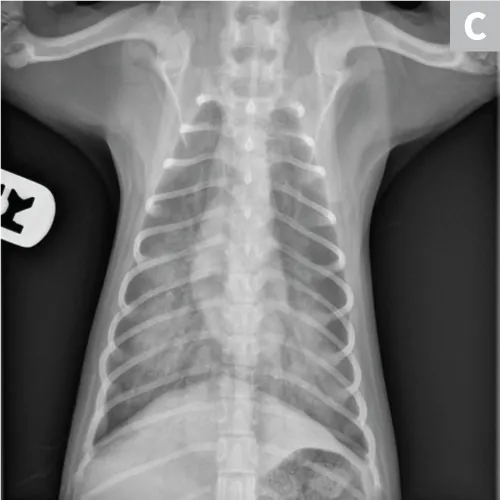

Pulmonary neoplasia may, on occasion, have a more diffuse nature. This is common with pulmonary lymphoma40 and is sometimes seen with carcinoma (author experience). Pulmonary lymphoma can have a rapid clinical course and mimic acute disorders. A diffuse, unstructured interstitial pattern is typically appreciated. Additionally, bronchointerstitial, alveolar, and nodular patterns may be observed (Figure 7).40

FIGURE 7

(A) Pulmonary lymphoma with a diffuse, patchy bronchointerstitial pattern confirmed on bronchoalveolar lavage and peripheral lymph node aspiration. (B) Pulmonary carcinoma with a diffuse, severe bronchointerstitial pattern confirmed on bronchoalveolar lavage and postmortem examination. Note: Pulmonary and hilar lymphadenopathy are not always present.